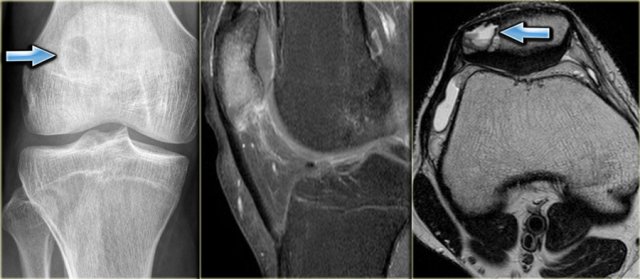

On the left a chondroblastoma located in the patella.

Discriminators :

- must be under age 30.

- must be in the epiphysis.